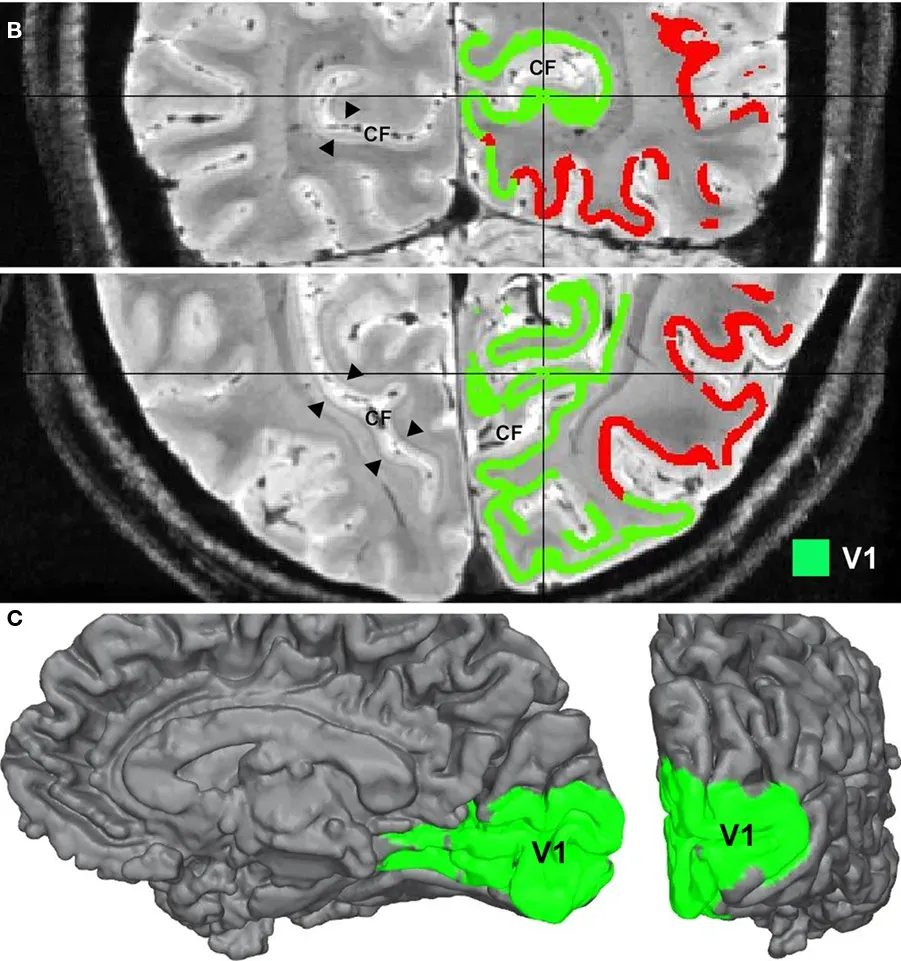

If you strip away the myths, what remains is a remarkably sophisticated visual system doing heavy lifting every second you are awake. Incoming information first hits the primary visual cortex in the back of the brain, gets unpacked into edges, colors, and shapes, and then flows forward into networks that recognize objects, faces, and scenes. When someone seems to “instantly” memorize a picture, what is really happening is a deep, coordinated burst of processing that binds visual details to context, emotion, and meaning. The hippocampus, a seahorse-shaped structure tucked in the temporal lobe, plays traffic controller, deciding which moments matter enough to consolidate into long-term storage.

In people with striking visual recall, brain scans often reveal stronger or more efficient communication between visual regions and memory hubs. Some show thicker or more active areas involved in imagery, suggesting they can replay internal pictures with unusual clarity on demand. Others appear to recruit additional networks linked to attention and executive control, allowing them to lock onto fine details instead of letting them fade into the background noise of daily life. It is less like having a high-resolution camera and more like having a team of meticulous archivists who tag, cross-reference, and file away what you see with obsessive care.

Neurodiversity adds another layer. Some autistic individuals, for instance, show exceptional pattern recognition and attention to visual detail, which can spill over into remarkable memory for certain types of information. People with synesthesia may literally “see” numbers or words in color, giving them an extra sensory hook for recall. Brain imaging often reveals structural and connectivity differences in these groups – not better or worse in a simple sense, but tuned differently, with some networks overdeveloped and others underused. Photographic-like memory may sometimes emerge from these nonstandard blueprints, reminding us that there is no single “normal” brain, only a wide landscape of possibilities.